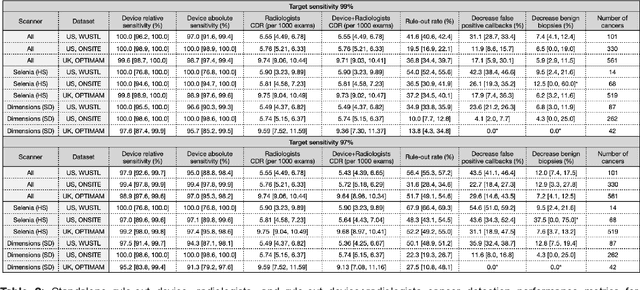

A deep learning algorithm for reducing false positives in screening mammography

Apr 13, 2022

Screening mammography improves breast cancer outcomes by enabling early detection and treatment. However, false positive callbacks for additional imaging from screening exams cause unnecessary procedures, patient anxiety, and financial burden. This work demonstrates an AI algorithm that reduces false positives by identifying mammograms not suspicious for breast cancer. We trained the algorithm to determine the absence of cancer using 123,248 2D digital mammograms (6,161 cancers) and performed a retrospective study on 14,831 screening exams (1,026 cancers) from 15 US and 3 UK sites. Retrospective evaluation of the algorithm on the largest of the US sites (11,592 mammograms, 101 cancers) a) left the cancer detection rate unaffected (p=0.02, non-inferiority margin 0.25 cancers per 1000 exams), b) reduced callbacks for diagnostic exams by 31.1% compared to standard clinical readings, c) reduced benign needle biopsies by 7.4%, and d) reduced screening exams requiring radiologist interpretation by 41.6% in the simulated clinical workflow. This work lays the foundation for semi-autonomous breast cancer screening systems that could benefit patients and healthcare systems by reducing false positives, unnecessary procedures, patient anxiety, and expenses.